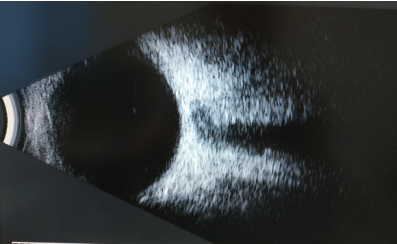

因为曾听说过眼前黑影致盲的例子,我马上去了眼科进行检查,结果显示双眼有线状混浊。当时为我诊疗的是医院里的眼科首席专家陈主任,他解释,我这样的情况是玻璃体混浊,也就是患了“飞蚊症”,是老年性玻璃体液化所致的。

△结果显示双眼有线状混浊